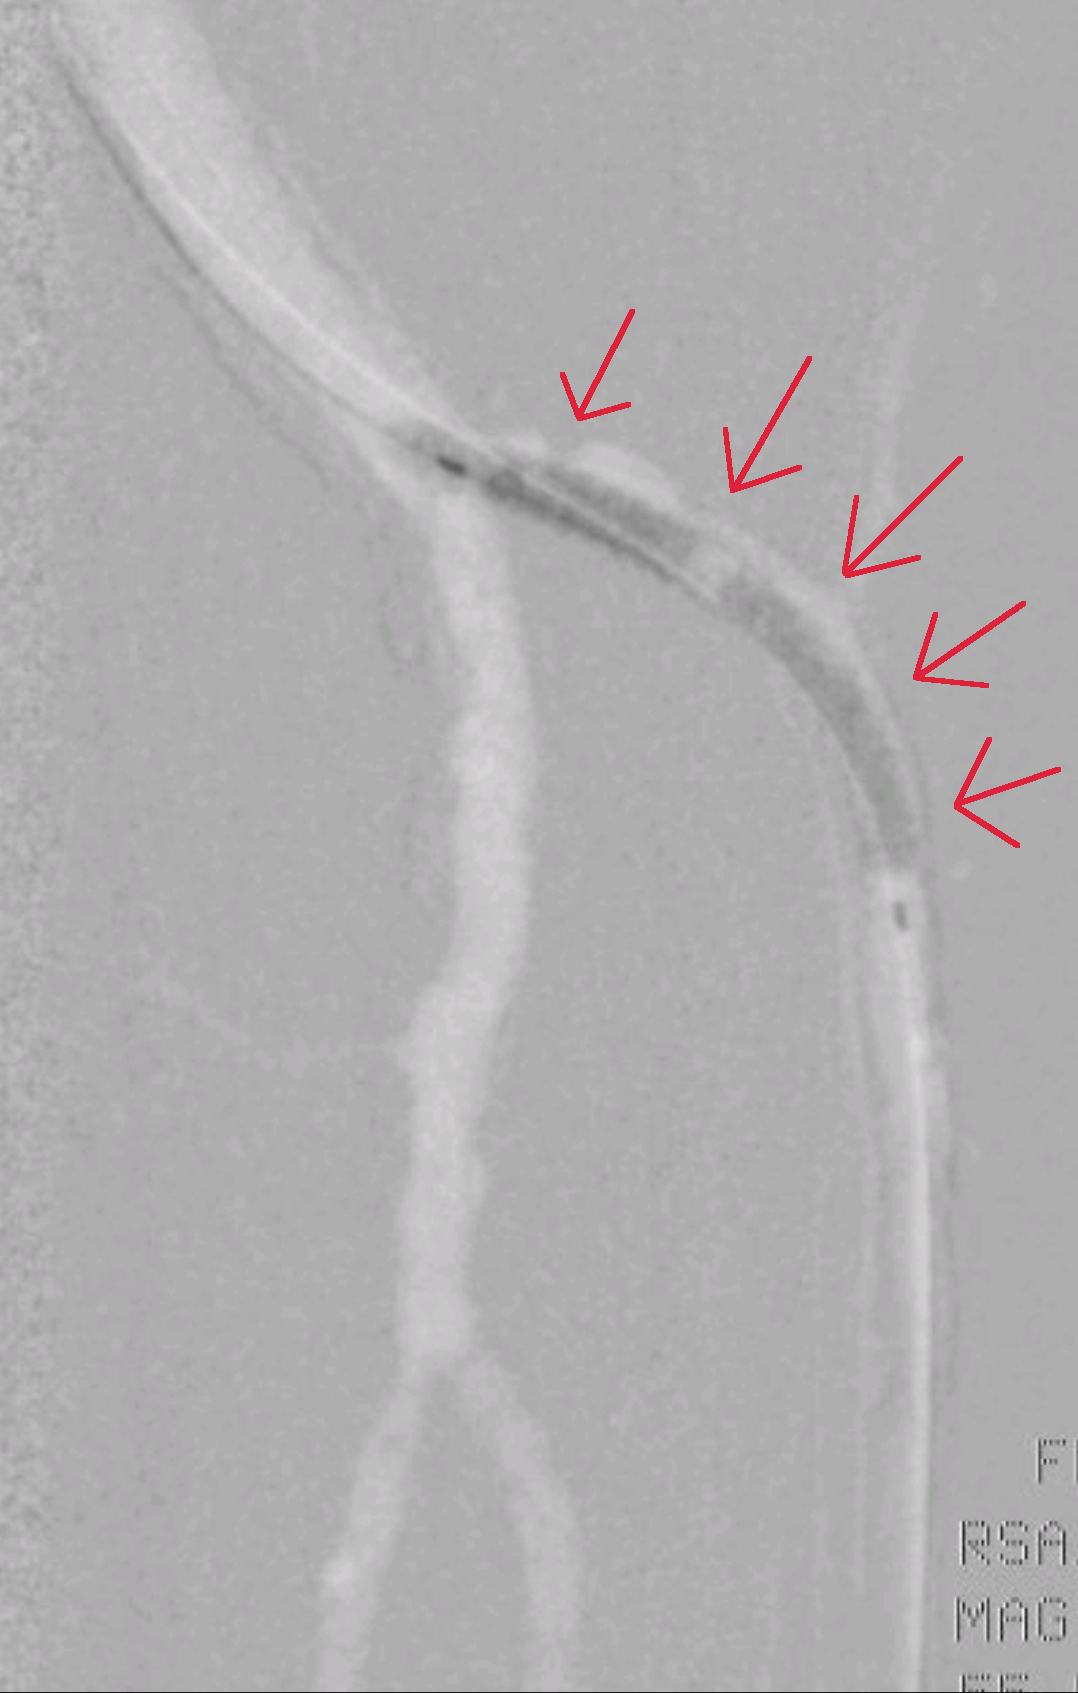

Širjenje žile z balonom (rdeče puščice), pripravlja se žila za namestitev žilne opornice, ki bo omogočala dolgotrajno prehodnost žile. Če žilo le razširimo in ne postavimo žilne opornice ima žila možnosti, da se bo kmalu ponovno zožila.